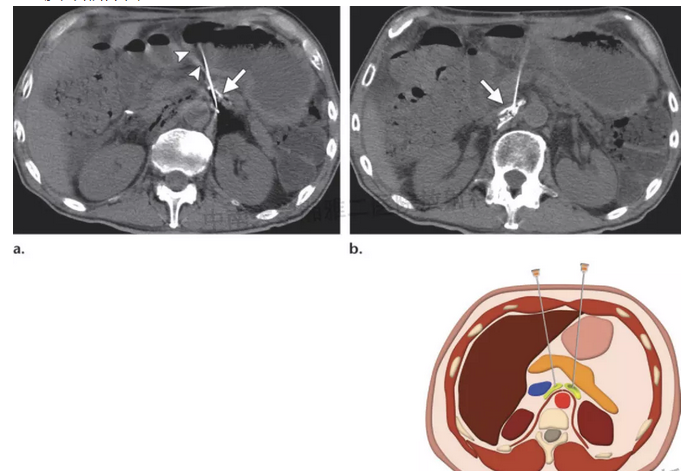

腹腔神经节(丛)消融术(celiac plexus neurolysis cpn)腹腔神经节(丛)